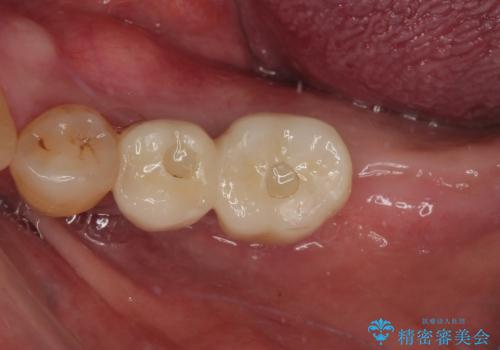

骨吸収が大きかったため、待機期間を必要としましたが、外科処置は初診時の抜歯も含めて3回に抑えることができ、半年の短期間で治療を終えることができました。